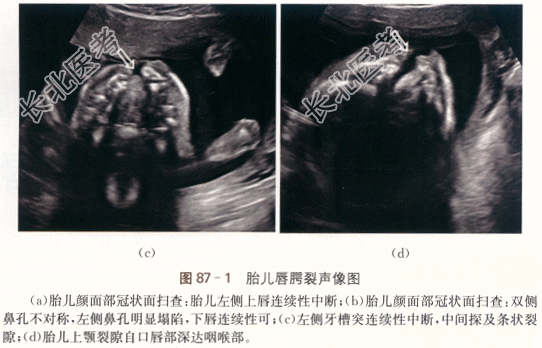

1.病史

患者,女性,23岁,孕24周2天,行常规产前检查。自诉一年半前因TSH4.18mIU/L在内分泌科会诊后予左甲状腺素(优甲乐)0.5粒qd口服,孕期随访,调整用药,现仍为0.5粒qd口服。既往2年前因“胎儿唇腭裂”引产一次。否认家族遗传病史。未行唐氏筛查检查。

二、影像资料

- 简答题1、患者的诊断及超声依据是什么?